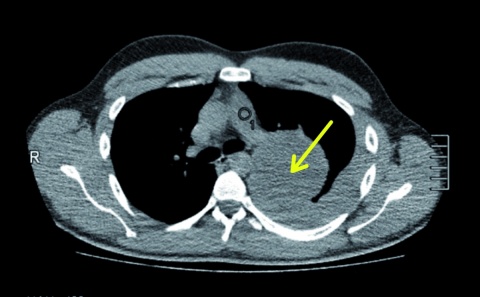

In der Nacht stellte sich ein 25-jähriger Mann in der zentralen interdisziplinären Notaufnahme des Bundeswehrkrankenhauses (BwKrhs) Ulm vor. Er war aus einer nahegelegenen Klinik aufgrund von atemabhängigen linkseitigen Thoraxschmerzen mit unklarem röntgenologischen Befund zugewiesen worden. Bei der Anamnese berichtete der Patient, dass er wenige Stunden vor der ersten Arztvorstellung beim Sport einen plötzlichen linksseitigen thorakalen Schmerz verspürt habe. Dieser sei persistent, atemabhängig und wurde von ihm mit einer Intensität von 8 (numerische visuelle Analogskala von 0 – 10) beschrieben. In einer Computertomographie des Thorax (diese wurde ohne Kontrastmittel als Trauma-CT durchgeführt, da zu diesem Zeitpunkt zunächst kein Verdacht auf das Vorliegen einer Tumorerkrankung bestand) war eine hypervaskularisierte Raumforderung von 9 x 9 x 11 cm im linken Oberlappen zu sehen. Ebenso wurde bei dieser Untersuchung der dringliche Verdacht auf einen Hämatothorax geäußert. Aufgrund einer möglicherweise erforderlichen thoraxchirurgischen Intervention mit gegebenenfalls notwendiger konsekutiver intensivmedizinischer Betreuung wurde der Patient zu uns verlegt.

Die stationäre Aufnahme erfolgte aufgrund der ausgeprägten Klinik und dem Verdacht auf das Vorliegen eines Hämatothorax. Hinzukam die thorakale Raumforderung mit unklarer Genese, deren Ätiologie abzuklären war. Zunächst ging man hierbei von einer eingebluteten Zyste aus; des Weiteren stand eine Neoplasie mit unklarer Differenzierung im Raum. Zur Histologiebestimmung wurden einige Methoden diskutiert, wobei sich eine Thorakoskopie als am besten geeignet ergab. Diese war im weiteren Verlauf geplant.